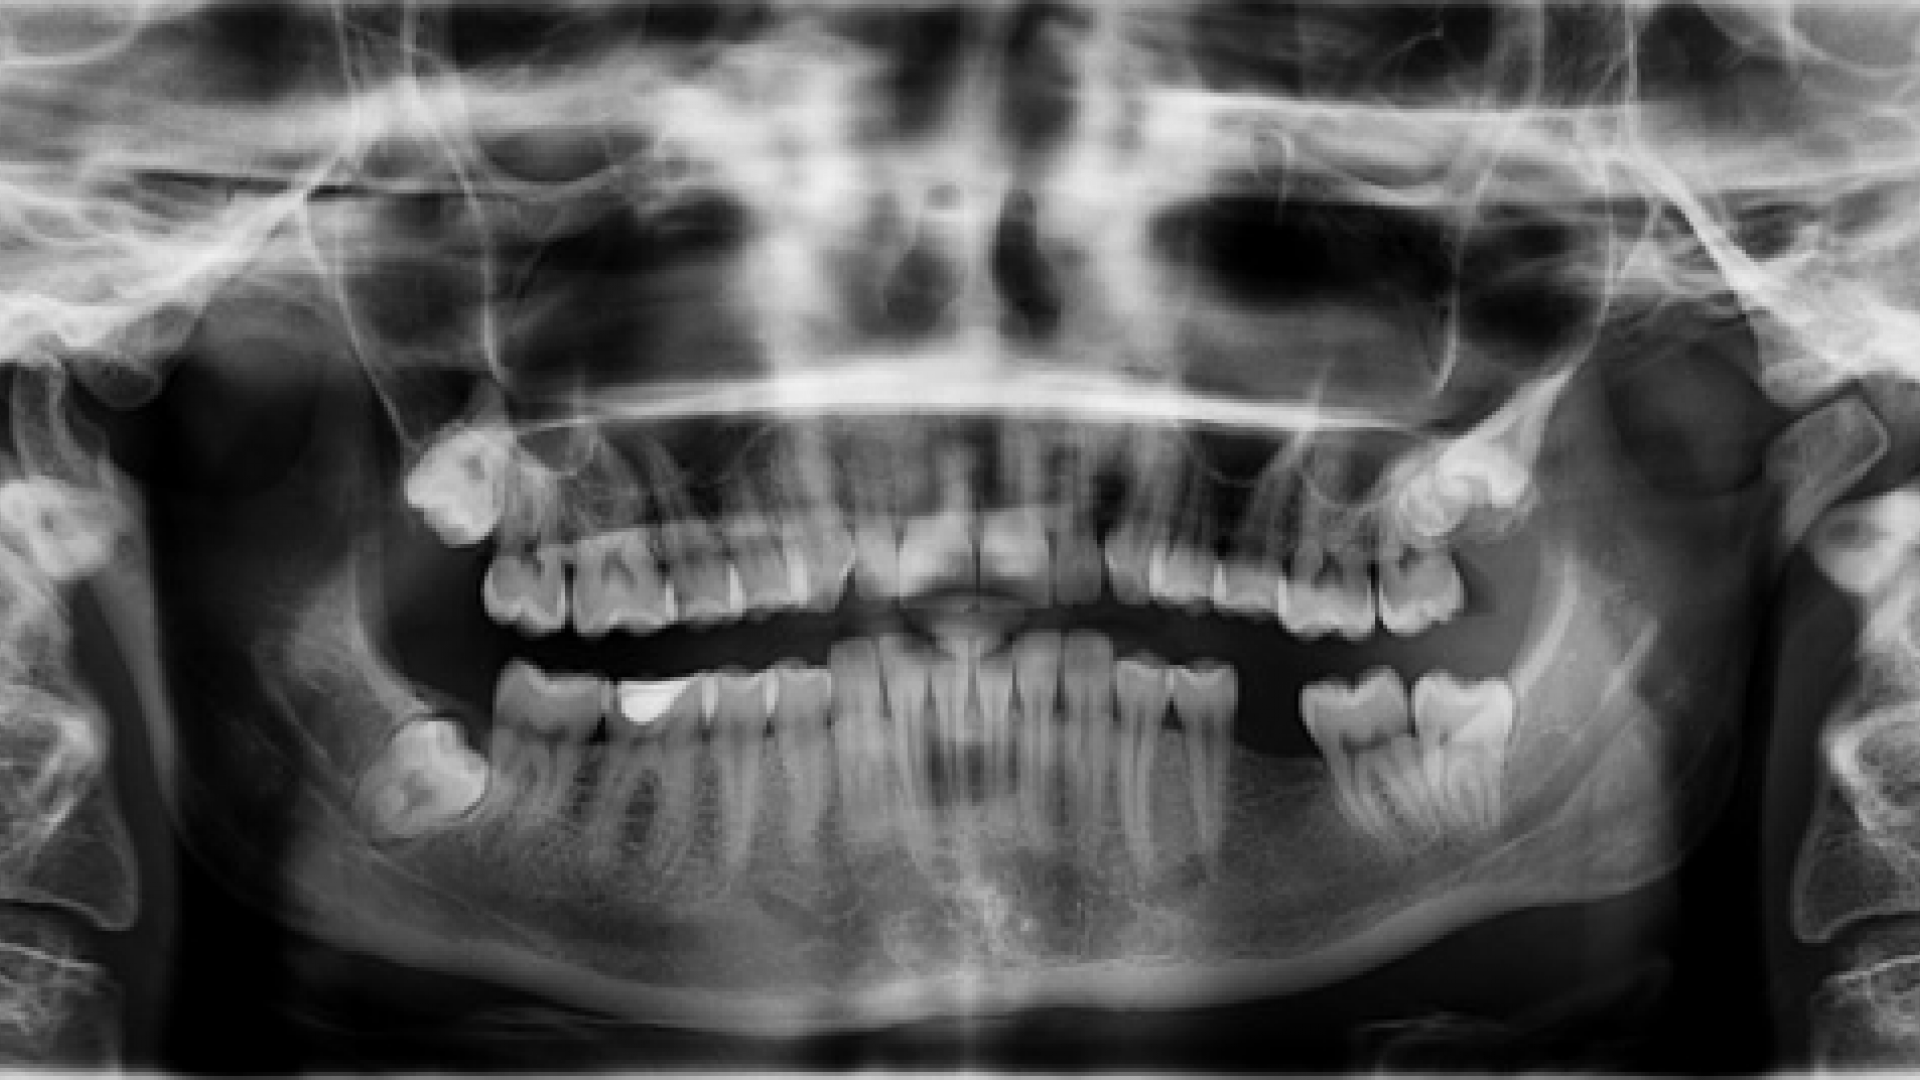

Wenn ein Zahn fehlt, sollten sich Betroffene bereits Gedanken um eine entsprechende Ersatzbehandlung machen.

pixabay.com, youlneverknow (CC0-Lizenz)